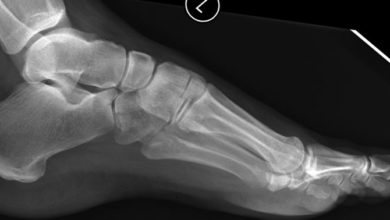

Futbolcu ayağı ( ayak bileği ön kısmı kemik sıkışma)

Ayak bileğinin ön kısmında tibia ve talusta tekrarlayan mikrotravmalar sonucu oluşan traksiyon osteofitleri ayakbileği hareketinin azalmasına ve ağrıya neden olur.…